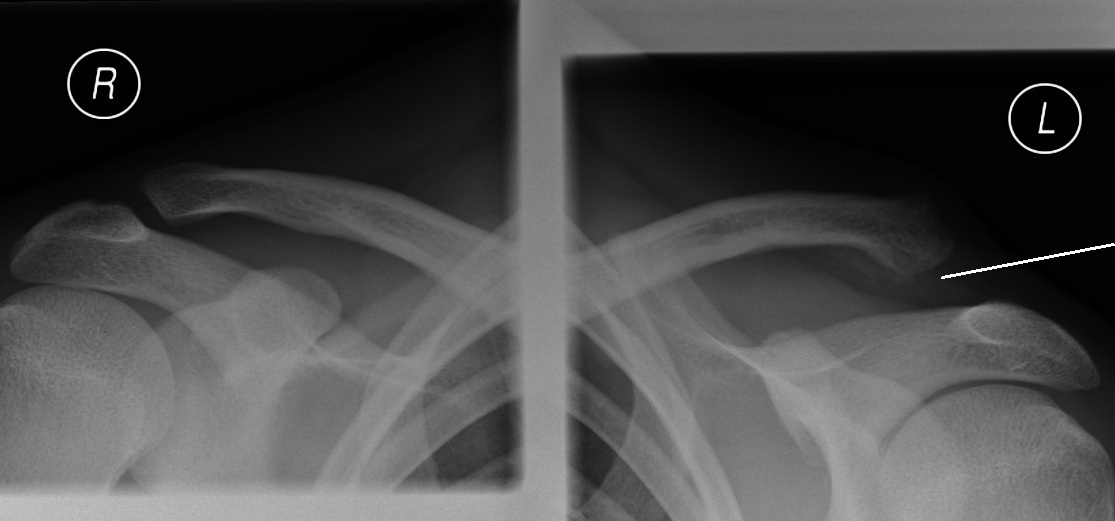

X rays (sometimes comparison X rays with the normal side are required).

X-ray of a normal right acromioclavicular joint and abnormal left acromioclavicular joint.

Note the increased gap on the left side.